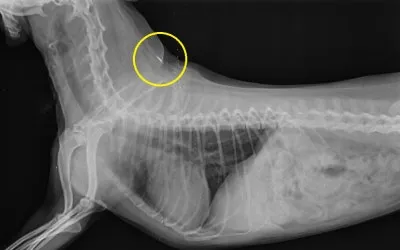

① 내장형 무선식별장치 개체 삽입(권장)

- 쌀알 크기의 작은 칩을 삽입하는 방식, 분실·훼손 위험 없음, 반영구적 사용 가능

[좌] 내장형 마이크로칩 형태(출처: 게티이미지코리아) [우] 내장칩 삽입 모습